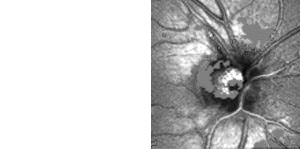

Neuroophthalmologische Diagnostik

Hilfreich ist das Gerät auch zum Nachweis, zur Quantifizierung und

zur Verlaufskontrolle bei Störungen der Pupillenmotorik von Kindern und

Erwachsenen.